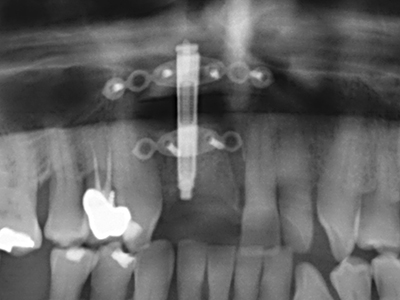

La piezochirurgia presenta altri vantaggi per quanto riguarda la raccolta di blocchi ossei. Oltre all'elevata precisione dell'osteotomia appena descritta, l'utilizzo di puntine per sega molto sottili permette di minimizzare in maniera significativa la perdita di materiale. È molto probabile che si verifichi una maggiore perdita di materiale durante la raccolta utilizzando puntine di strumenti più spessi, in particolare delle frese Lindemann (Lakshmiganthan, Gokulanathan et al. 2012). La separazione basale, necessaria in particolare per i trapianti di blocchi nella zona retromolare, viene semplificata grazie a seghe specificatamente progettate di forma rettangolare; di conseguenza la piezochirurgia è considerata una procedura precisa, semplice e sicura per la raccolta di blocchi di osso nella zona retromolare (Happe 2007) (figg. 1-12).